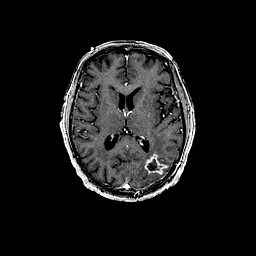

Glioma overlay -- Slice #63

[Home][Help][Clinical] Slice 63